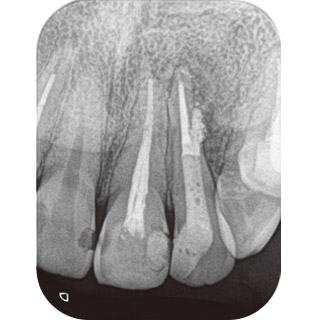

症例2-4 2回目の来院時にはサイナストラクトは消失、2回の治療で終了。根管充填時のX線写真。 -

症例2-5 再根管治療6ヵ月後のX線写真。骨組織の回復が確認できる。